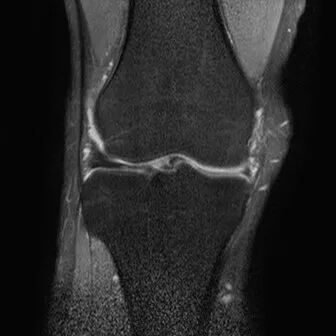

半月板水平撕裂

1、水平撕裂

2、较少见3、III级高信号与胫骨平台平行,到达半月板的游离缘或一侧关节面

(半月板水平撕裂)